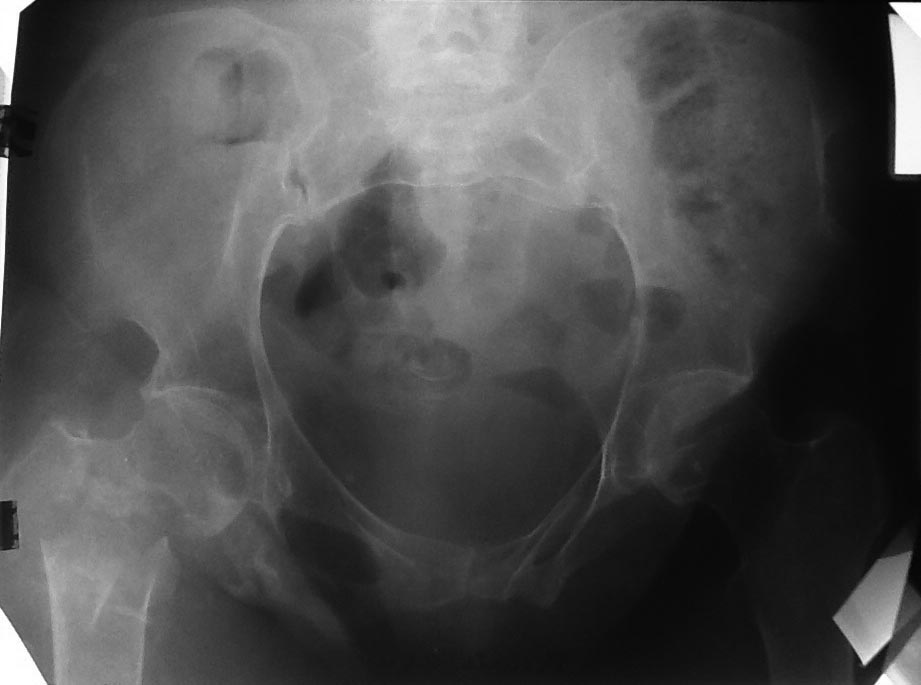

Патологический перелом проксимального отдела бедра |

Пациентка 47 лет, нижняя параплегия, "колясочница"', но достаточно активна- самостоятельно себя обслуживает- моется в ванной, готовит и т. д. Спинальная травма у пациентки более 20 лет назад.

Чувствительность до колен сохранена. В 90-х годах был выполнен остеосинтез диафизарных переломов бедра и голени с противоположность стороны пластинками. Заживлетние ран без осложнений.

У нас вызывает сомнение в синтезе из-за низкого качества кости, к тому же пациентка "колясочница".